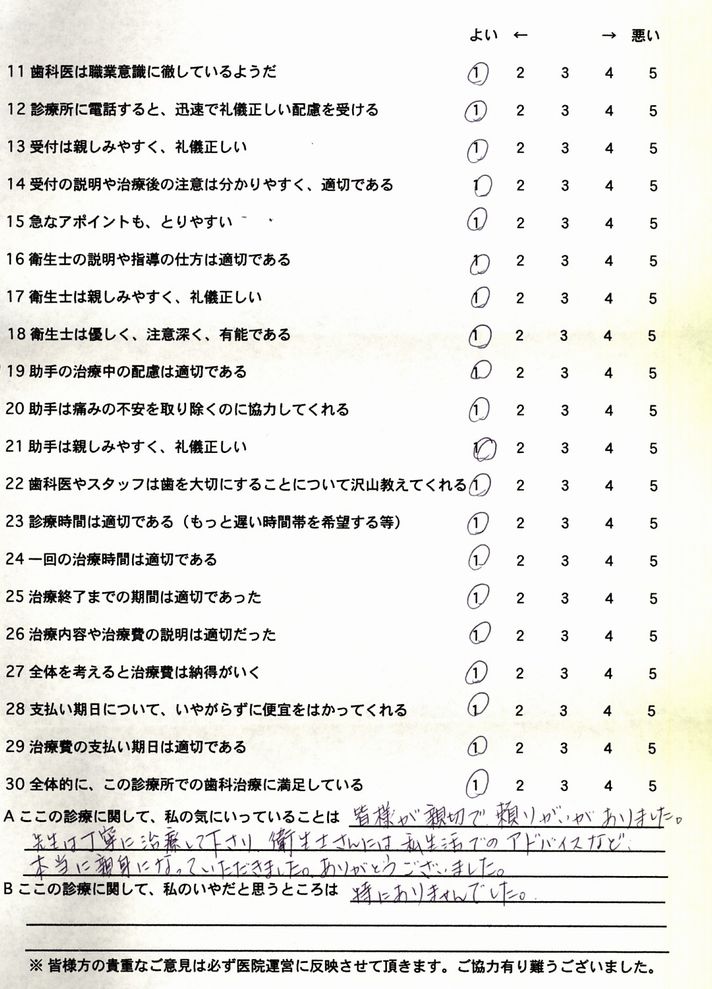

いつかは来るだろうマスクをしなくてもよくなった時のことを考えると憂鬱な毎日でした。

時間もお金もかかりましたが、今、マスクをしなくても歯ッピーな笑顔ができるようになり、仕事も

新天地を迎えることが出来ました。本当に良かったですね。

ホーカベ歯科クリニック 歯科医師 波々伯部重俊